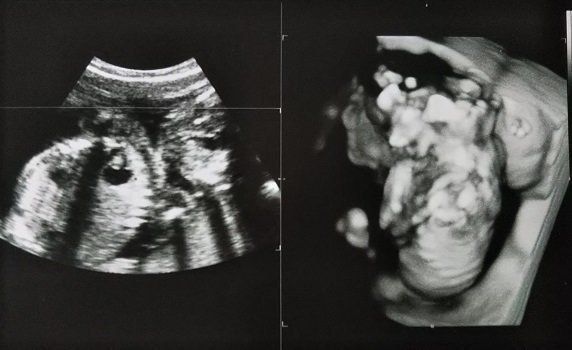

まきさんの妊娠19週目のエコー写真 赤ちゃんの心室や膀胱の様子もエコーで確認できました。

妊娠19週目。性別がわかるかもしれないということで、主人も一緒について来た健診のときのエコー写真です。エコーを見せてもらって、先生から「心臓の部屋は4つ。膀胱におしっこも溜まっているから、腎臓にも異常なし。背骨もしっかりしていて体重等も標準。いい子です」と言っていただいてひと安心。帰りの車で主人に「先生、女の子って言っていたね」と言われてビックリ!聞き逃していた…。主人曰く「先生は女の子でまちがいないとも言っていたよ」とのこと。帰りに本屋さんに寄って、女の子の名前辞典を買いました。